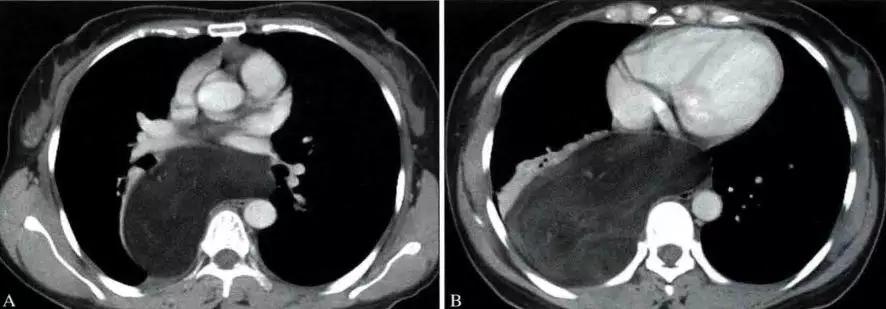

影像表现

胸腺癌影像表现为前纵隔大的肿块,通常边界不清楚,边缘不规则或分叶状,常侵犯并推移邻近结构。常有坏死、出血和(或)囊性变,10% ~ 40%在CT上可见灶状钙化。常侵犯心包、胸膜并出现心包和胸腔积液

胸腺类癌影像表现与常见胸腺上皮肿瘤相仿。当前纵隔肿块伴有库欣综合征时,诊断上应首先考虑为胸腺类癌。MRI上T2WI呈明显呈高信号,可能提示神经内分泌癌的诊断